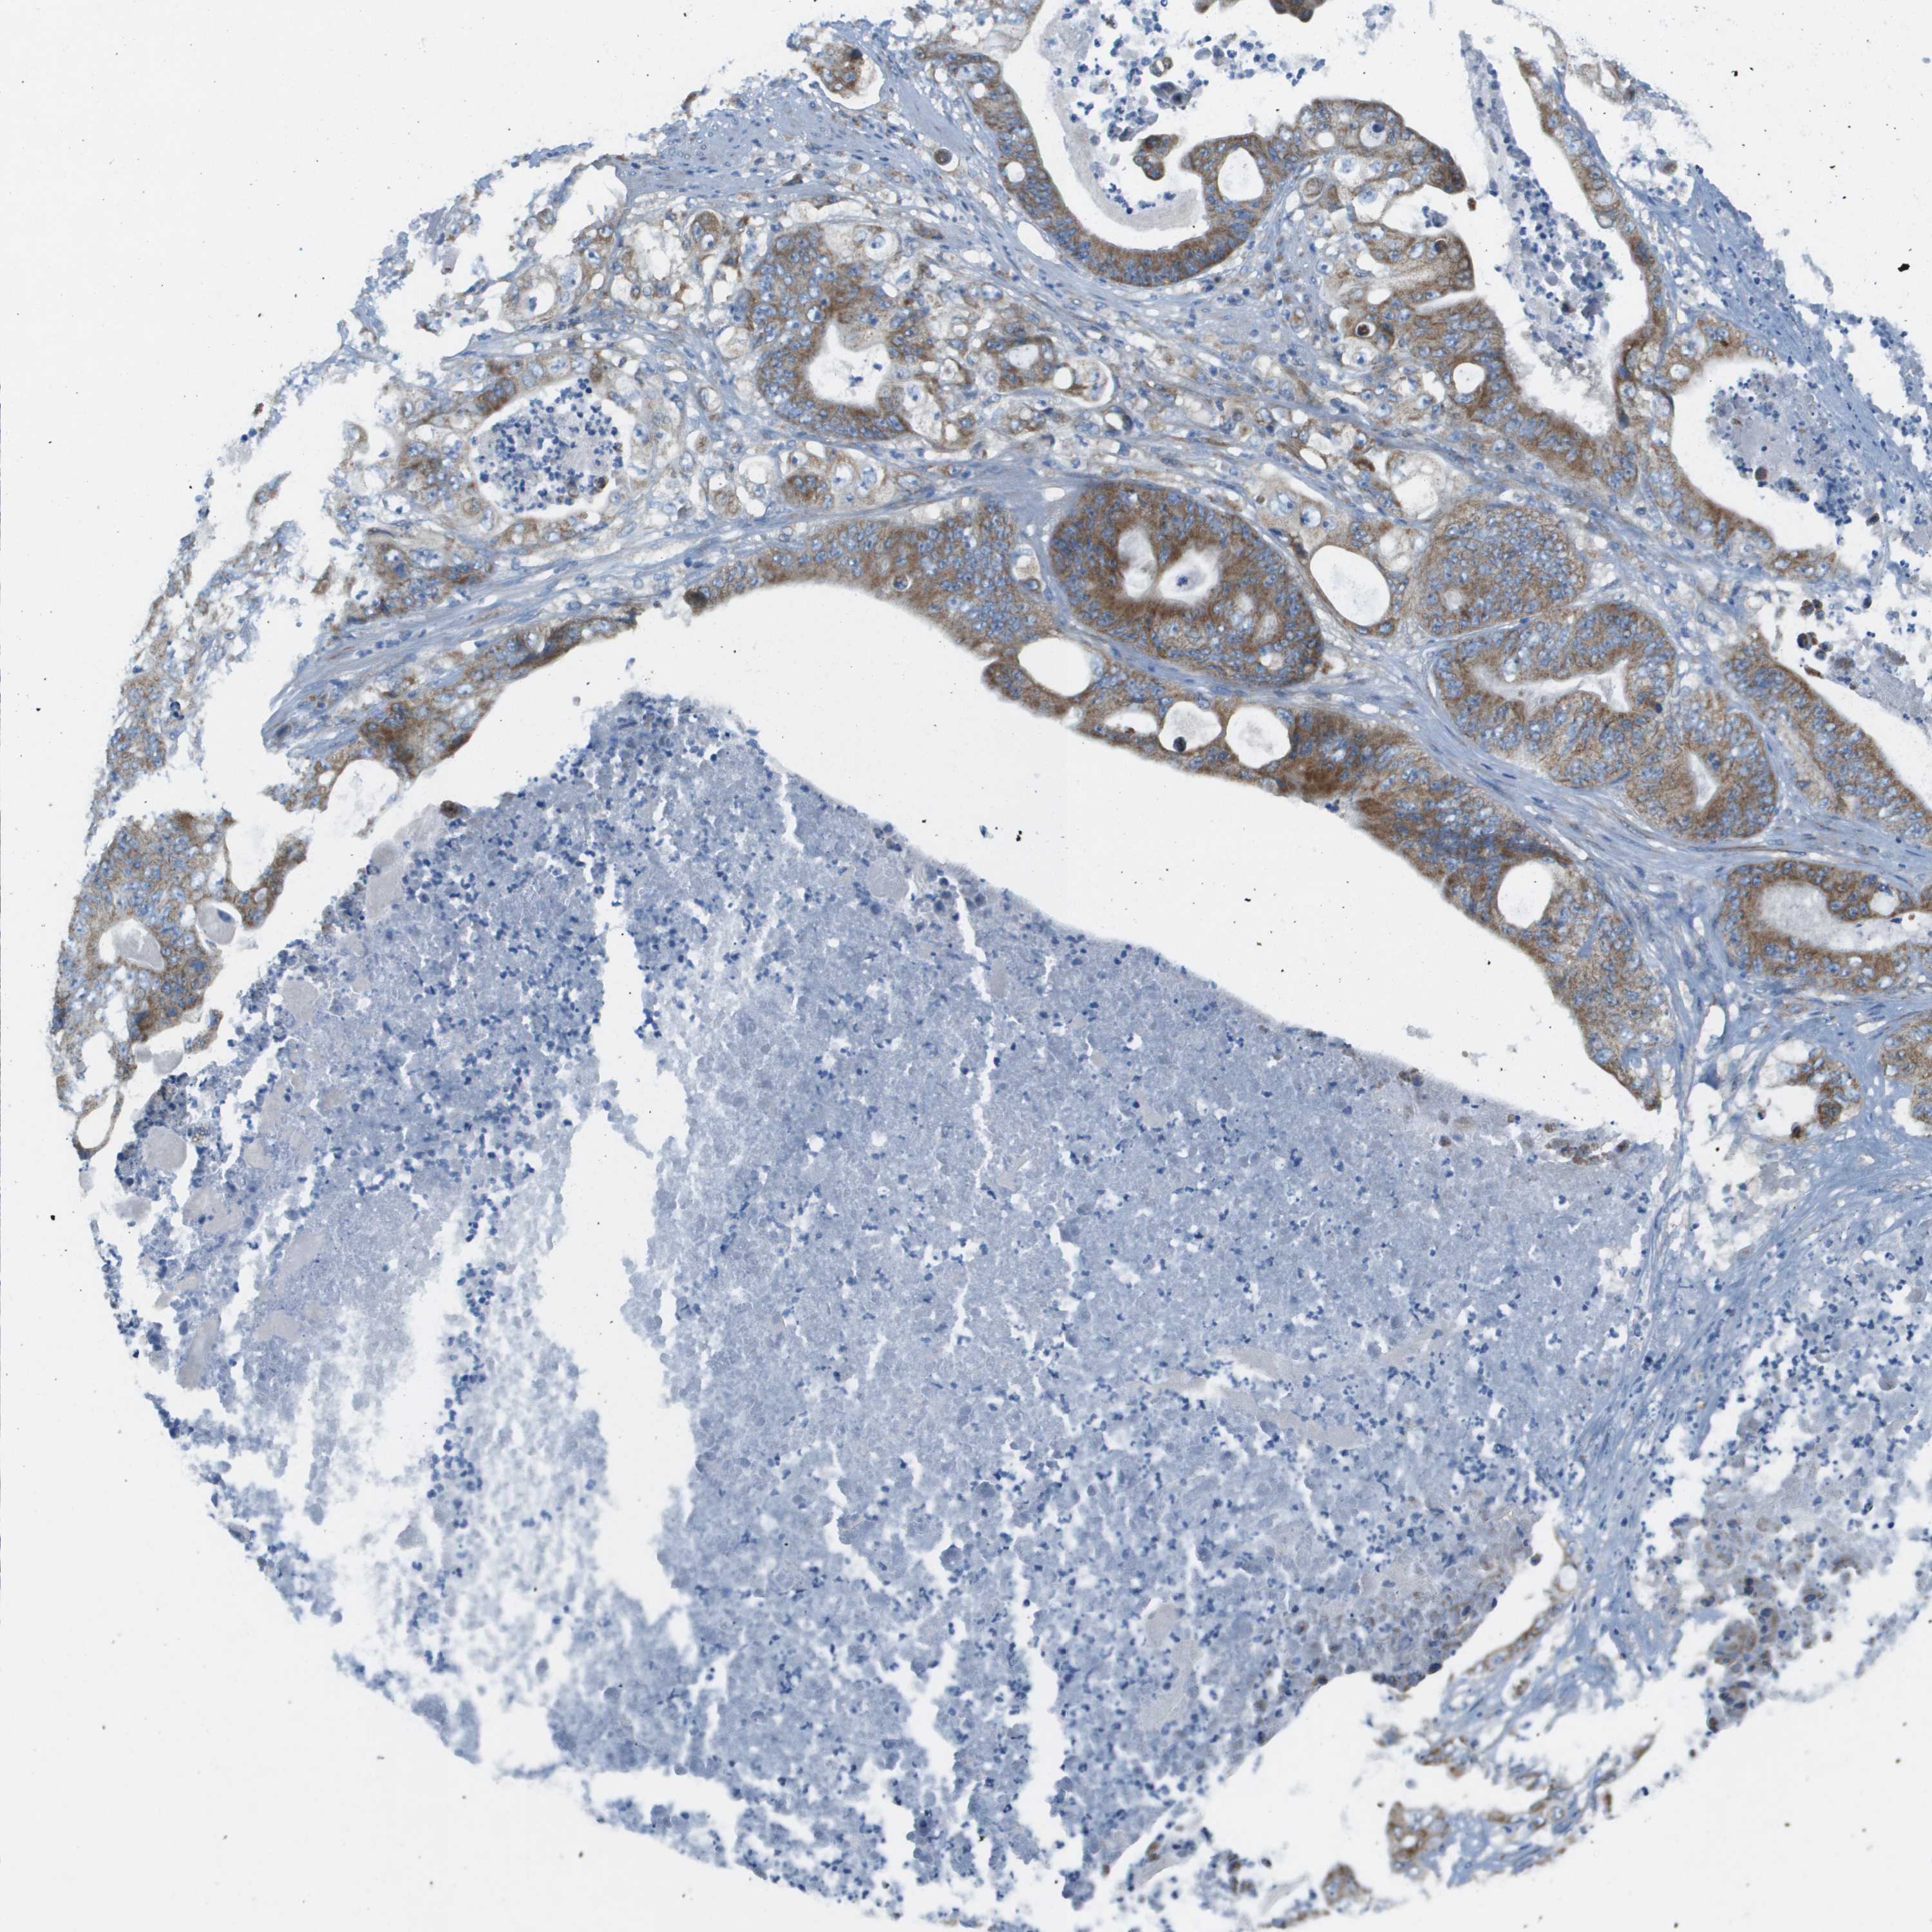

STOMACH CANCER - Protein expressioni

A mouse-over function shows sample information and annotation data. Click on an image to view it in a full screen mode. Samples can be filtered based on level of antibody staining by selecting one or several of the following categories: high, medium, low and not detected. The assay and annotation is described here.

Antibody stainingi

Antibody staining in the annotated cell types in the current human tissue is reported as not detected, low, medium, or high, based on conventional immunohistochemistry profiling in selected tissues. This score is based on the combination of the staining intensity and fraction of stained cells.

Each image is clickable and will lead to virtual microscopy that enables deeper exploration of all samples and also displays staining intensity scores, fraction scores and subcellular localization as well as patient and tissue information for each sample.

Antibody HPA017160

Staining

High

Medium

Low

Not detected

Intensity

Strong

Moderate

Weak

Negative

Quantity

>75%

75%-25%

<25%

None

Location

Nuclear

Cytoplasmic/membranous

Cytoplasmic/membranous,nuclear

Adenocarcinoma, NOS